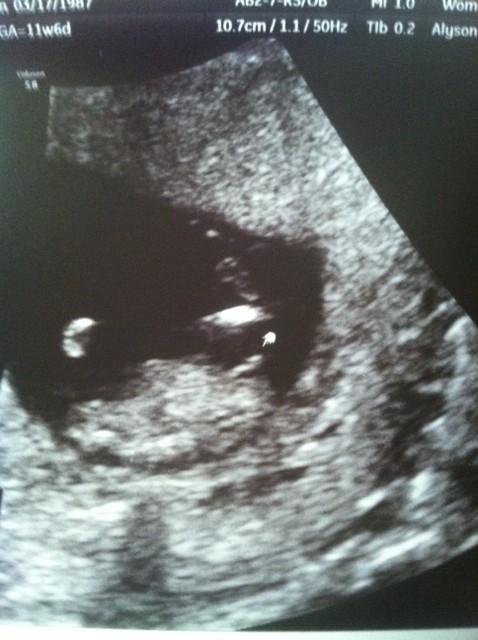

I had my ultrasound today and I'm 11w6d based on my last AF but baby measured 12w1d. Any guesses? Thanks for looking! :)